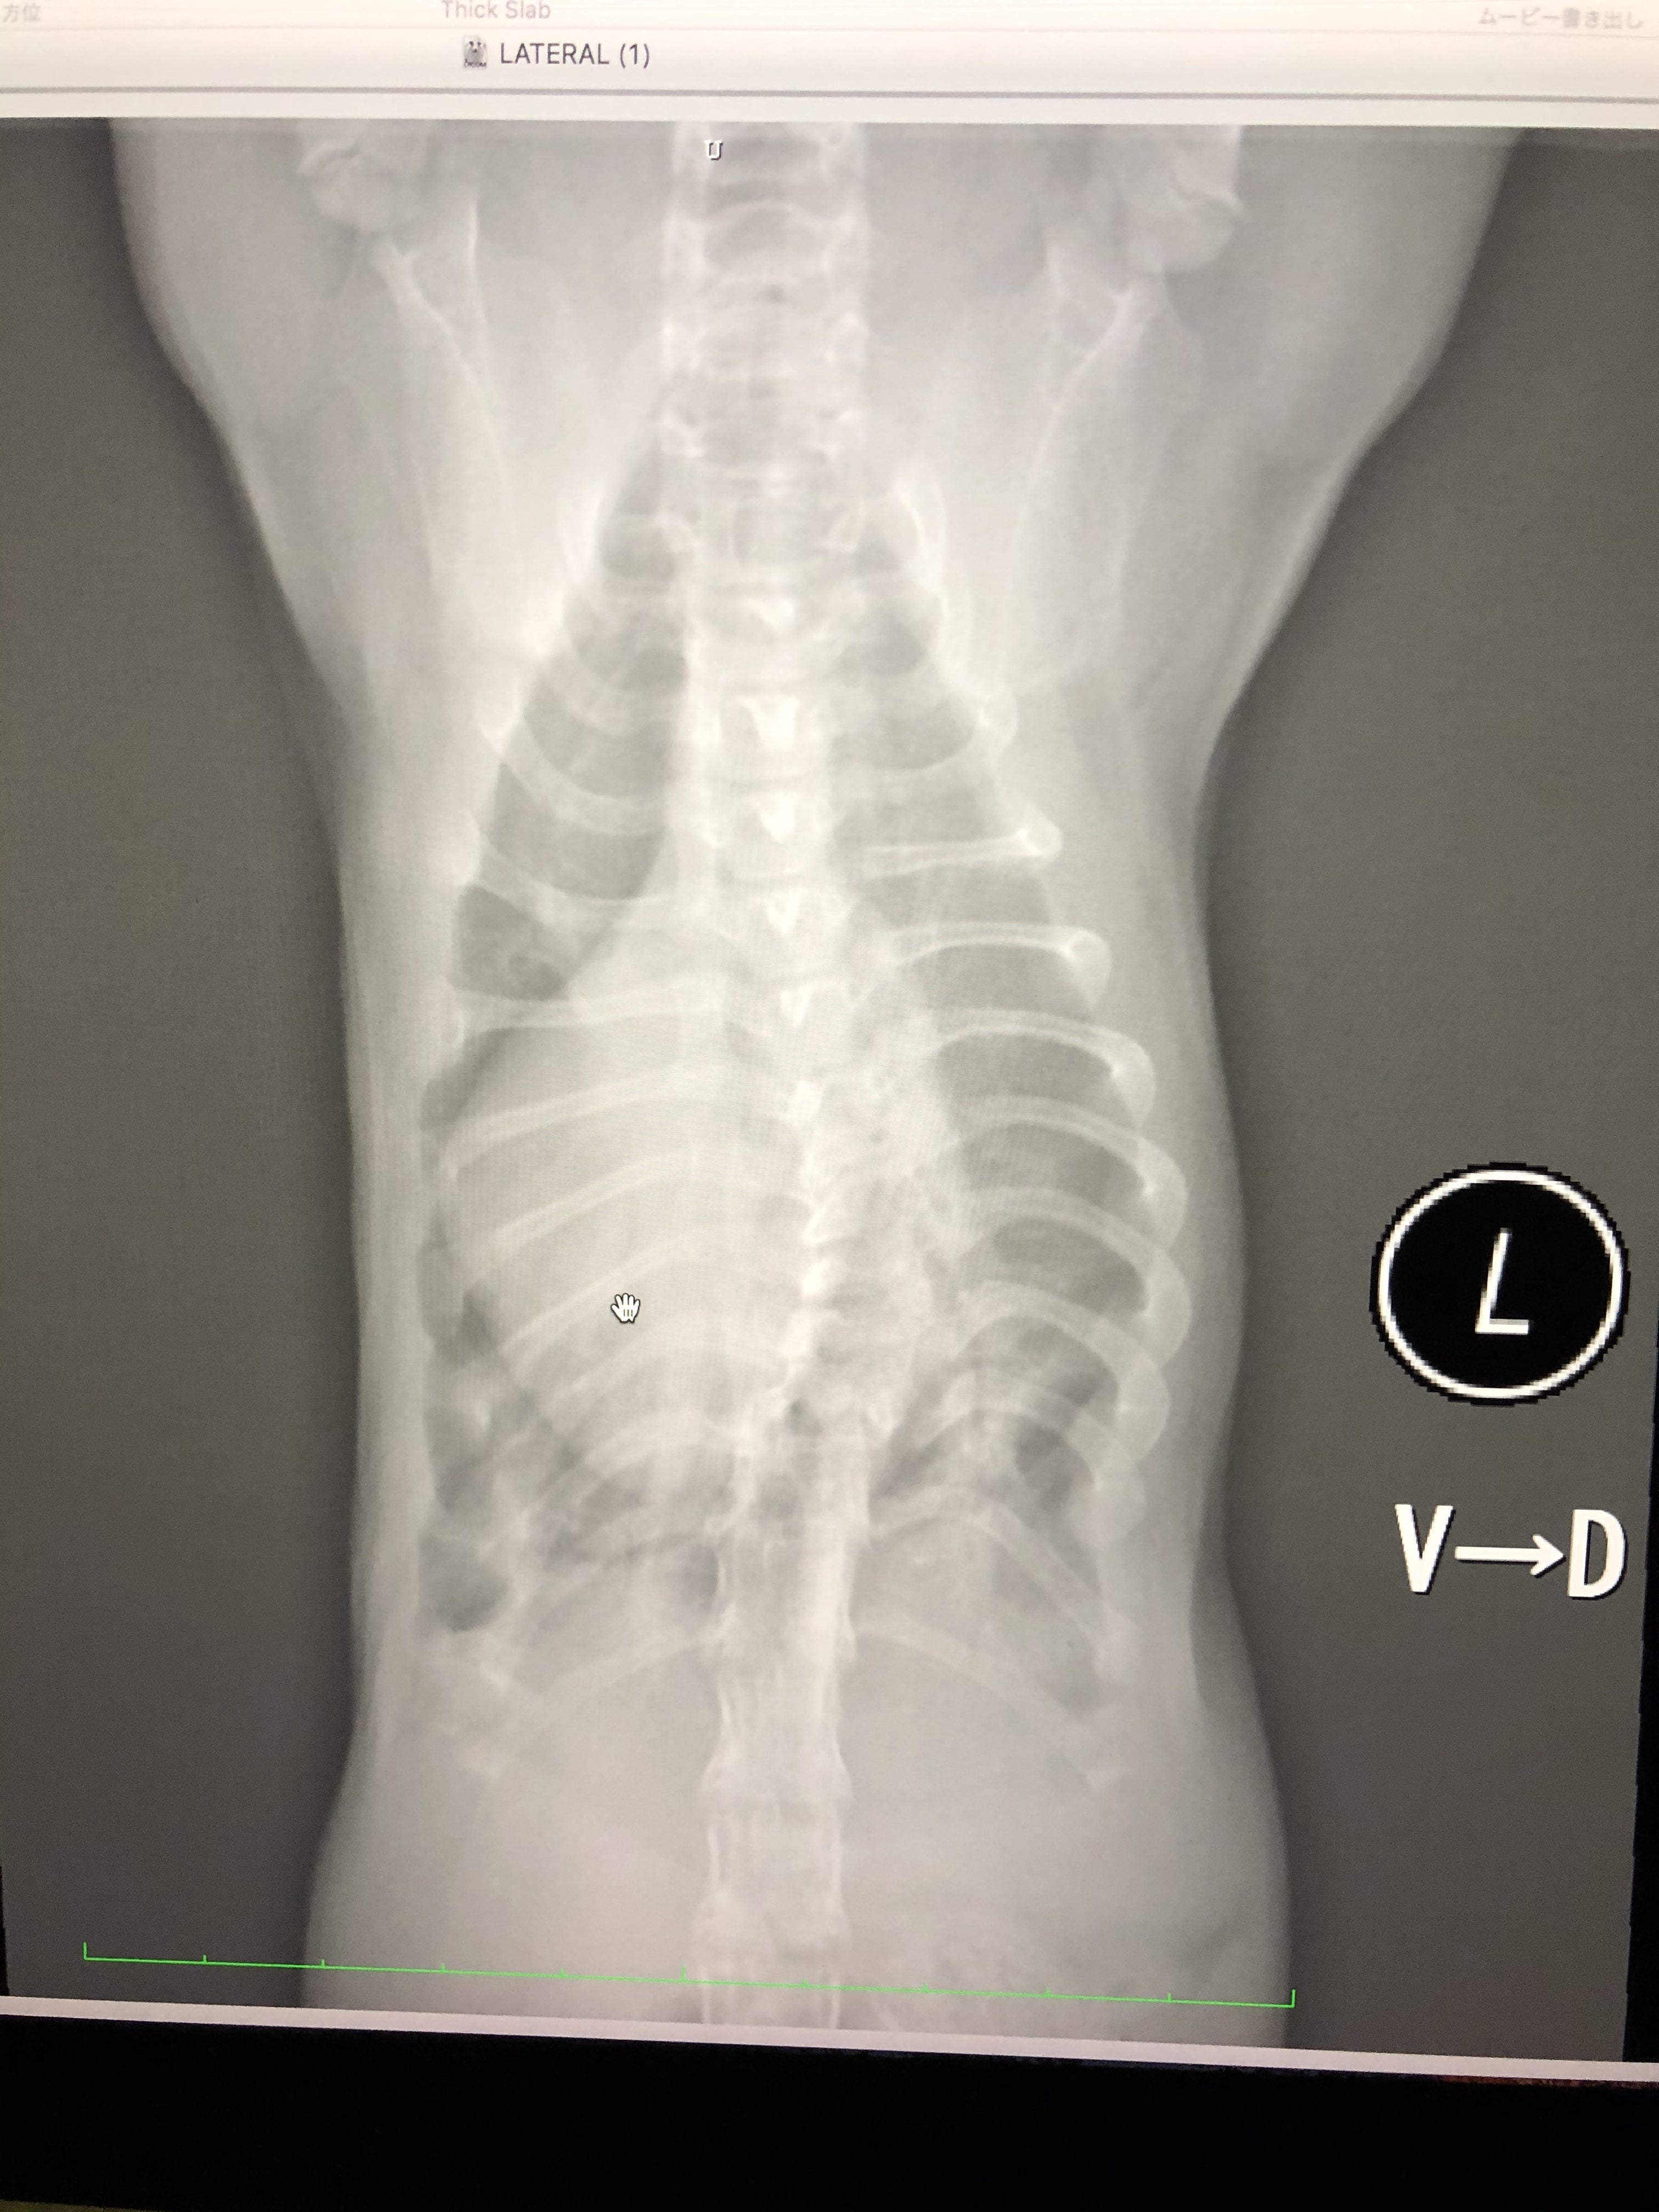

レントゲン、エコー、心電図などなど、いろんな検査をしてもらいました。

春までもたないと言われていた背骨肋骨による胸の空間は愈史郎の成長がゆっくりだったため、悪化していませんでした。

しかし、好転しているわけでもなく、危険は残っていると言われました。

先生の説明では、子猫で体が小さすぎるため、検査結果を見ても、現状ではなんとも言えなく、定期的に検査に行くことになりました。

脊椎の変形が、今後下半身麻痺になるかもしれないと言われました。

(画像は最新の検査時のレントゲンです。)